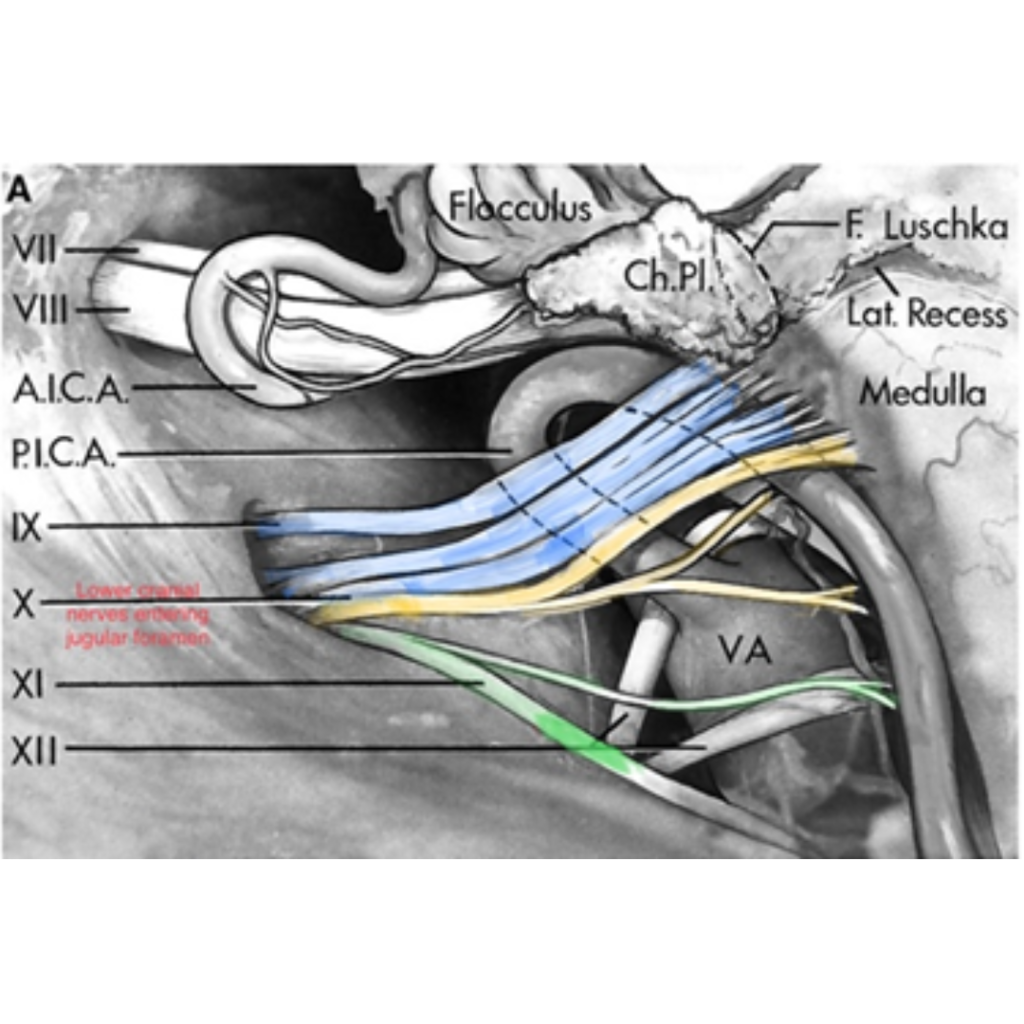

Which nerves are called as Lower cranial nerves:

1. 9th: Glossopharyngeal

2. 10th: Vagus

3. 11th: Spinal accessory nerve

Lower Cranial nerves entering jugular fossa

Spinal Accessory Nerve